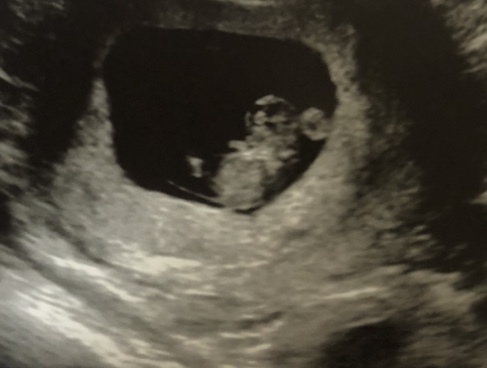

Hey everyone,

I’ve been a bit quiet for a while, mostly because I’ve been feeling so worried about everything going wrong but I had my follow up early scan today (9+2) and everything looks ok. It’s even got a little pillow so looks comfy and getting settled in. Feeling a bit relieved and maybe very slightly more optimistic... maybe!

Lovely scan @Viletta, must feel good to get out of the first trimester 😊

Oh, very nice photographs @Viletta and @dobbiefreeelf! So nice to see the little ones in there, isn't it? We can follow how they are developing. Bit sad now that I let DH convince me not to have a 10-week scan, but I guess it just makes me wait for the 12-week one even more.

@DobbieFreeElf aww the baby on the scan looks so cute!! And your doggie too!